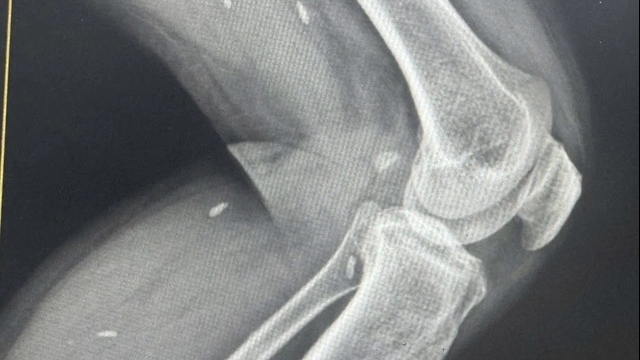

Trẻ được chẩn đoán dị tật tim bẩm sinh là Tứ chứng Fallot có kèm theo tình trạng tăng áp lực động mạch phổi và ống động mạch đã đóng. Với diễn biến của trẻ không giống với những trường hợp được chẩn đoán là tứ chứng Fallot thông thường, Ban lãnh đạo Trung tâm đã tiến hành hội chẩn cấp cứu cho bệnh nhân.

Kết quả siêu âm tim của cháu trước khi ra viện cho thấy tim của cháu H. hoạt động giống tim bình thường và áp lực động mạch phổi đã trở về bình thường.